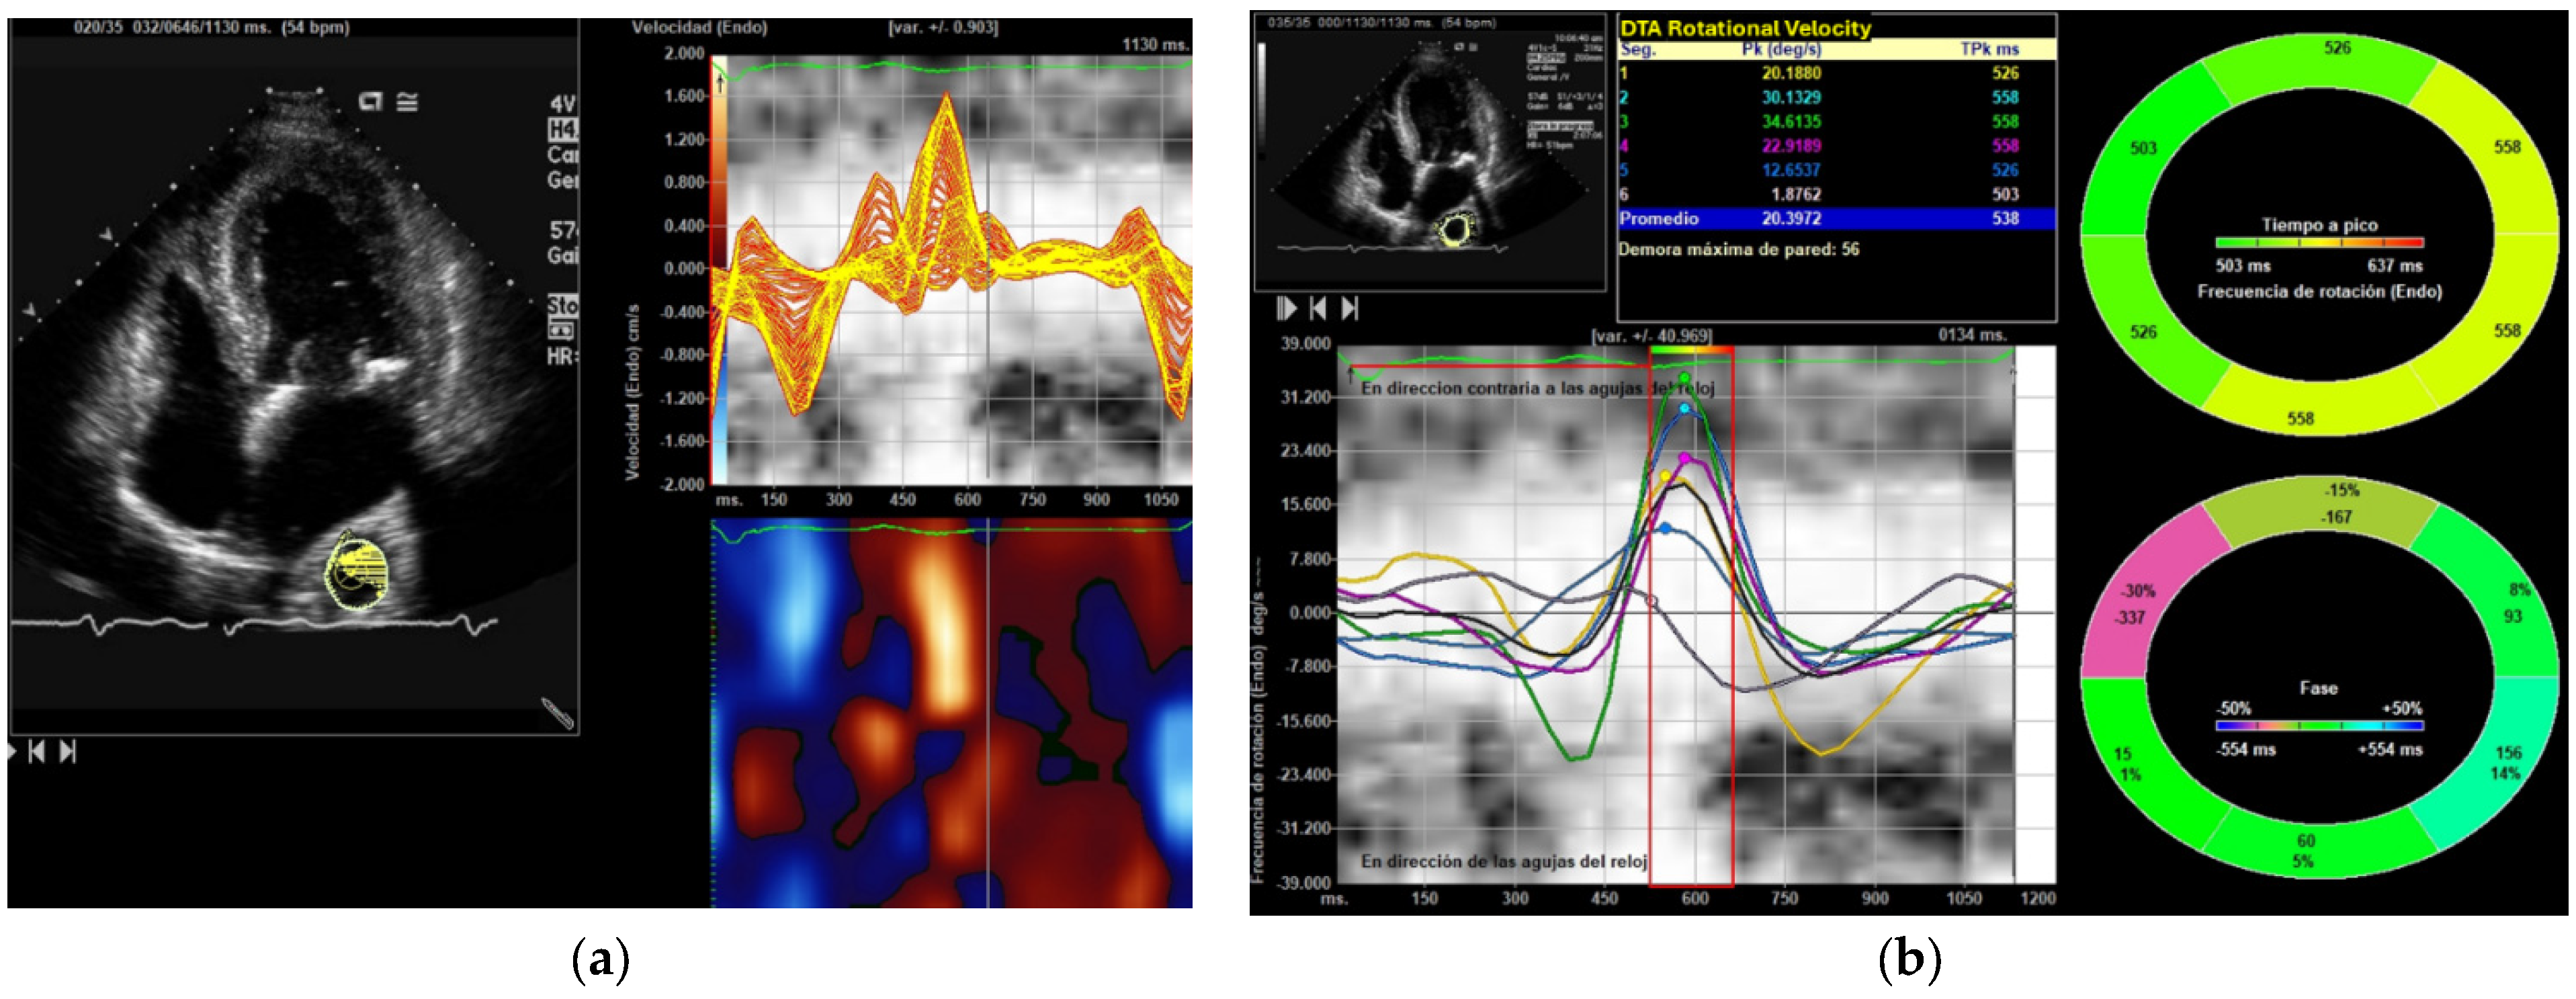

2.7. Image Acquisition and Processing